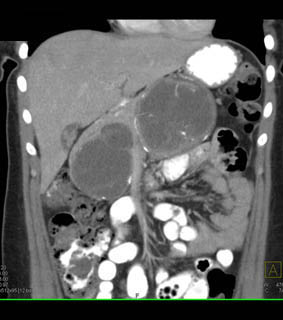

The best dx in this 2oish yr old woman is?

pseudocyst

SPEN tumor

cystadenoma

abscess